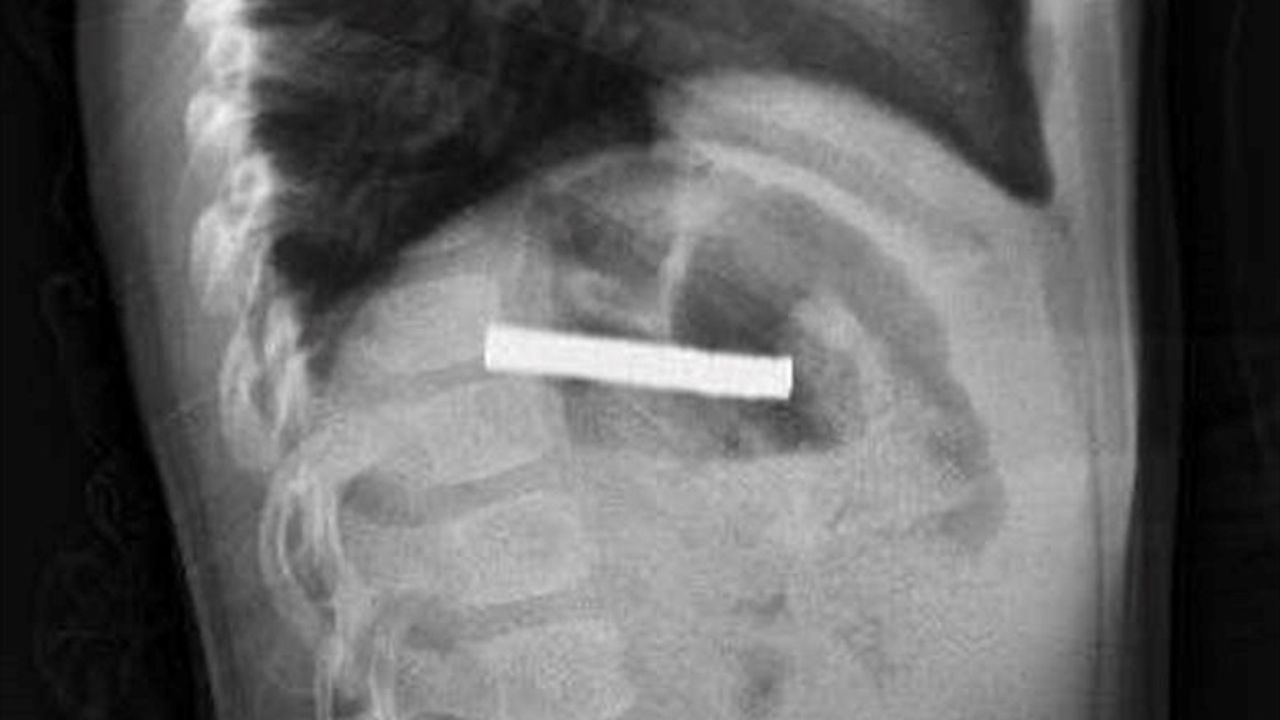

Elazığ'da 3 yaşındaki bir çocuk, oyun oynadığı sırada bulduğu 19 mıknatısı yuttuktan sonra rahatsızlanarak hastaneye kaldırıldı. Bu durum, Fırat Üniversitesi Hastanesi'nde gerçekleştirilen başarılı bir operasyonla son buldu.

Fırat Üniversitesi Çocuk Gastroenteroloji Hepatoloji ve Beslenme Bilim Dalı Başkanı Prof. Dr. Yaşar Doğan, burada yaptığı muayenelerde mıknatısların çocuğun yemek borusunu tıktığını belirledi. Doğan ve ekibi, çocuğun yemek borusundaki mıknatısları çıkarırken, işlem sırasında bazı hasarların oluştuğunu ancak iyi bir müdahale ile durumun kontrol altına alındığını ifade etti. "Mıknatıslar, hastanın midesine alındı ve oradan özel bir file ile çıkarıldı. İşlemden sonra çocuğu gözlem altında tuttuk ve sabah aile kendi isteğiyle taburcu olmak istedi," dedi.

Elazığ'da 3 yaşındaki çocuğun yuttuğu ve yemek borusunu tıkayan 19 mıknatıs, Fırat Üniversitesi Hastanesi'nde yapılan başarılı bir operasyonla çıkarıldı.